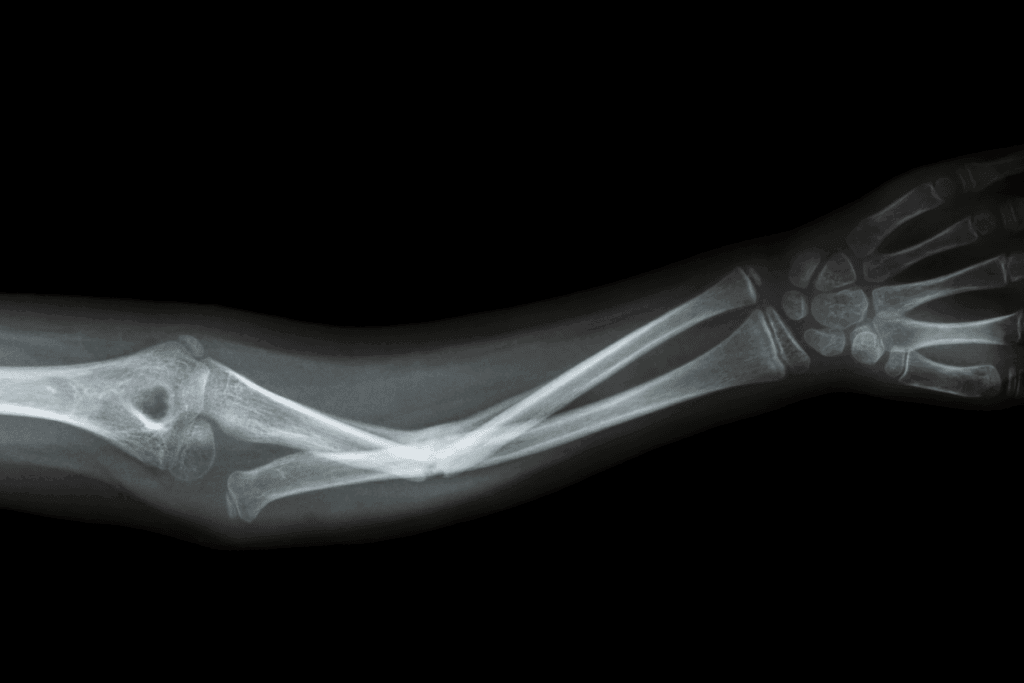

Dislocated Radius and Ulna

The radius and ulna bones form the elbow joint. A dislocation happens when these bones are pushed out of place. This can result from a fall or a direct hit to the elbow.

Symptoms include severe pain, swelling, and difficulty moving the elbow. Treatment involves immediate medical care to fix the dislocation and keep the joint stable. Sometimes, surgery is needed to repair damaged tissues.

Complex Elbow Dislocations

Complex elbow dislocations involve bone dislocation, fractures, or significant ligament damage. These are severe injuries needing detailed treatment, often surgery to fix the joint and repair damaged areas.

Rehabilitation after a complex elbow dislocation is vital for strength and mobility. Physical therapy is a key part of the recovery process.